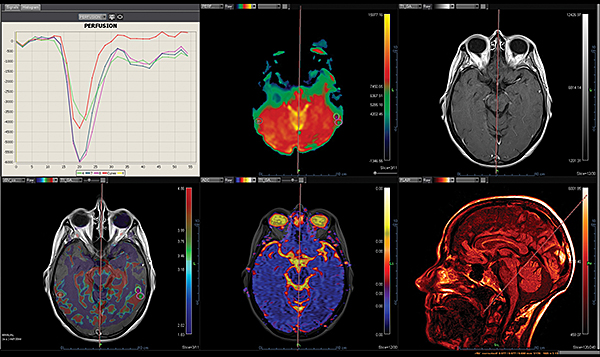

Перфузія DSC Perfusion

Додаток DSC Perfusion обчислює оптимізовані параметричні карти (rBV, rBF, TTP, MTT, TMAX, tMIP) із сирої перфузійної серії та забезпечує алгоритм для корекції ефектів розповсюдження контрастної речовини, обчислюючи карту проникності. Ця програма підтримує нерегулярний вибір часу та складається з наступних модулів: автоматична або ручна обробка arterial input function (функції артеріального наповнення), автоматична сегментація фону, чотири методи деконволюції (sSVD, cSVD, oSVD та байезівський) та алгоритм миттєвої корекції руху.

Незалежно від важкості невідкладного стану, ці додатки надають радіологам прямий доступ до звіту про інсульт в найкоротші терміни. Ці додатки включають інформацію про кровотік за допомогою унікальних динамічних порогових карт перфузії для візуальної оцінки гіпоперфузованих ділянок та використання методу Байєса для зменшення дози контрасту наполовину для перфузійного дослідження мозку.

Додаток Brain Tumor пропонує автоматизовану покрокову обробку, включаючи кількісний мультипараметричний аналіз. Ця програма також включає оптимізований алгоритм корекції витоку контрастної речовини для підвищення точності оцінки DSC MР-перфузії.

Додаток Neuro інтегрований у розширену візуалізацію Vitrea і забезпечує спеціальні протоколи для пухлини мозку та розширені протоколи інсульту, які забезпечують швидку оцінку захворювань головного мозку.

Обчислює оптимізовані параметричні карти (rBV, rBF, TTP, MTT, TMAX, tMIP) із первинної перфузійної серії

Використовує автоматизований та настроюваний робочий процес

Включає повністю автоматизовану поетапну обробку для пацієнтів з пухлинами мозку, включаючи кількісний та якісний мультипараметричний аналіз

Забезпечує корекцію витоку контрасту та створення карти K2 rBV